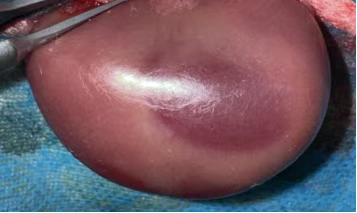

930ba3d6-16db-4763-9cb7-7a7e244a4958.png

松开动脉夹,待肾脏恢复红润(确认再灌注成功),逐层缝合,术后青霉素抗感染。